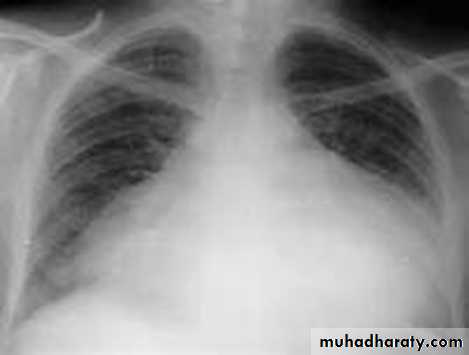

Slide 17Severe chest trauma by car accident1- What does the x ray show?2- What make the neck veins distended